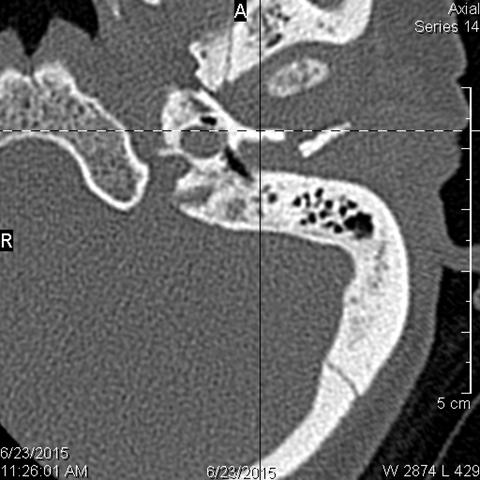

Mandible and Temporomandibular Joints